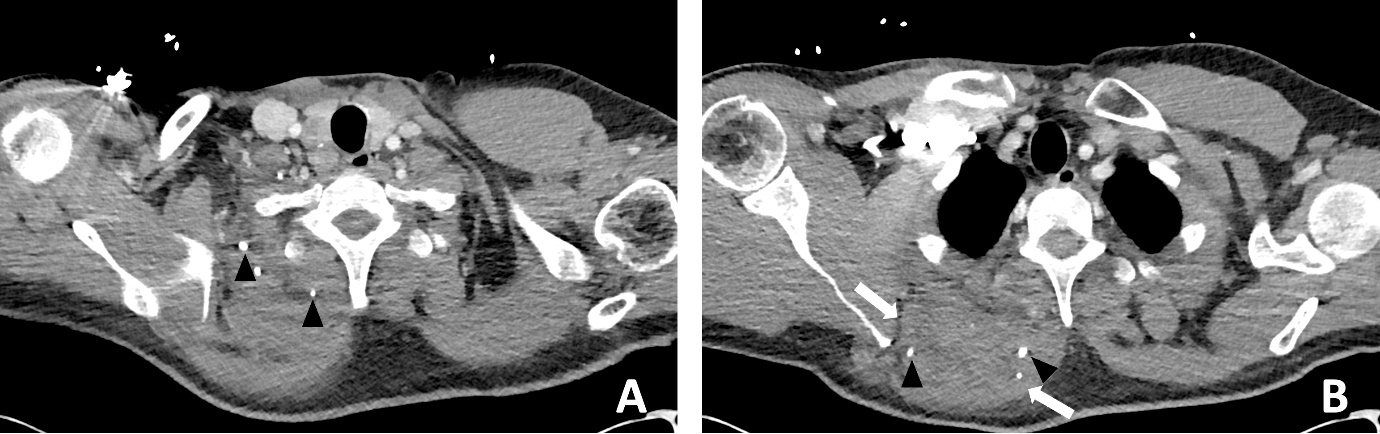

A previously well 47-year-old male presented to the emergency department with worsening atraumatic right shoulder pain and malaise. He was septic with a white blood cell count of 13.4 × 109/L and C-reactive protein of 489 mg/L. A chest CT reported a ‘large ill-defined heterogeneous density mass lesion within the upper medial posterior chest…with small volume fluid and subcutaneous fat stranding’. Internal hyperdense foci were interpreted as calcification or possible foreign bodies (Figure 3). The patient was admitted to the Intensive Care Unit (ICU) and placed on vasopressors support. The plastic surgery team was consulted to provide an opinion on urgent surgical management.

In retrospect, the presence of intramuscular phleboliths on CT in the cases presented above was the best clue to the diagnosis of an infected VM. Phleboliths occur in approximately 30 per cent of VMs.15 Intramuscular phleboliths have a limited imaging differential diagnosis and are generally taken to be pathognomic of VM.16 Radiologist and clinician awareness of this rare presentation of VMs is important; if intramuscular phleboliths are identified, the diagnosis of VM should be raised and the use of MRI may further assist in the diagnosis. If clinical doubt remains in an acutely unwell patient, prompt surgery to exclude necrotising soft tissue infection is prudent.

Timely surgical exploration is indicated in septic patients where necrotising soft tissue infection cannot be excluded. However, it is important to consider rare conditions that may present similarly, such as infected VMs. The presence of intramuscular phleboliths on CT, especially in a child, is the best imaging clue to this unusual diagnosis and should not be overlooked.